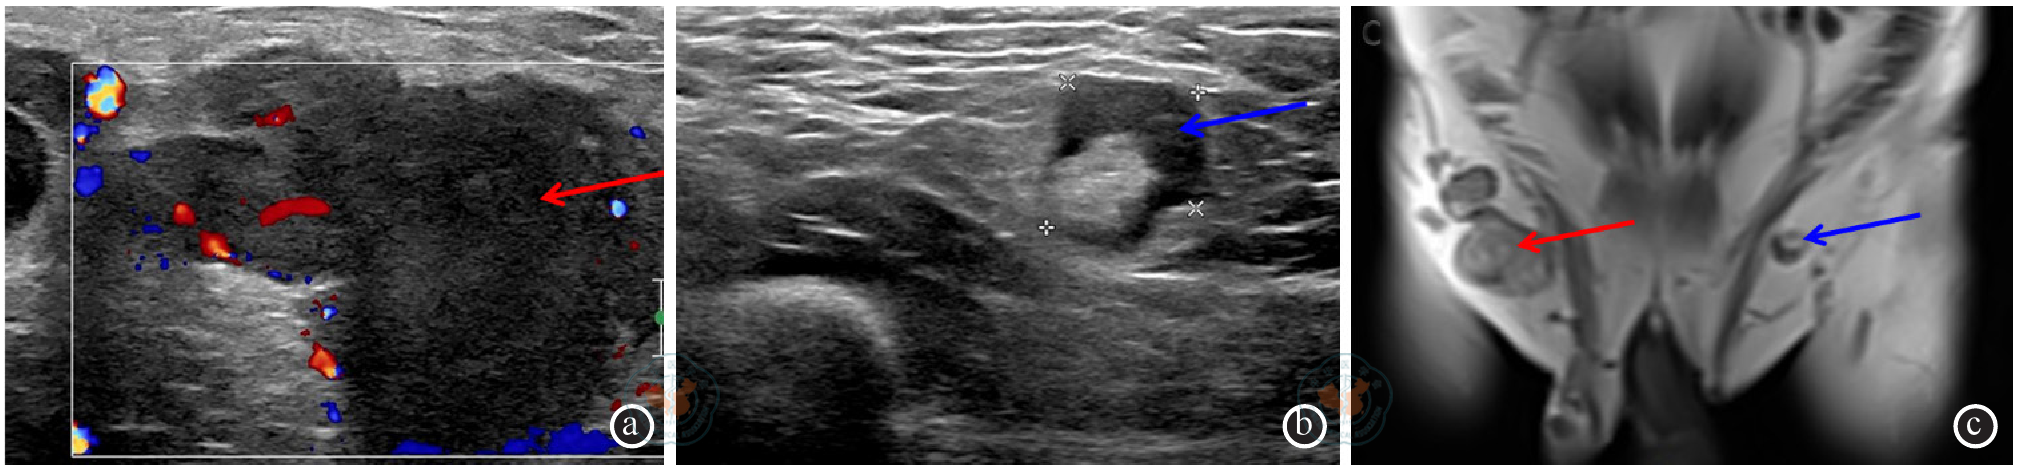

图5 阴茎癌患者新辅助治疗后右侧腹股沟区淋巴结明显缩小注:红色箭头示化疗前融合淋巴结,蓝色箭头示化疗后缩小的淋巴结